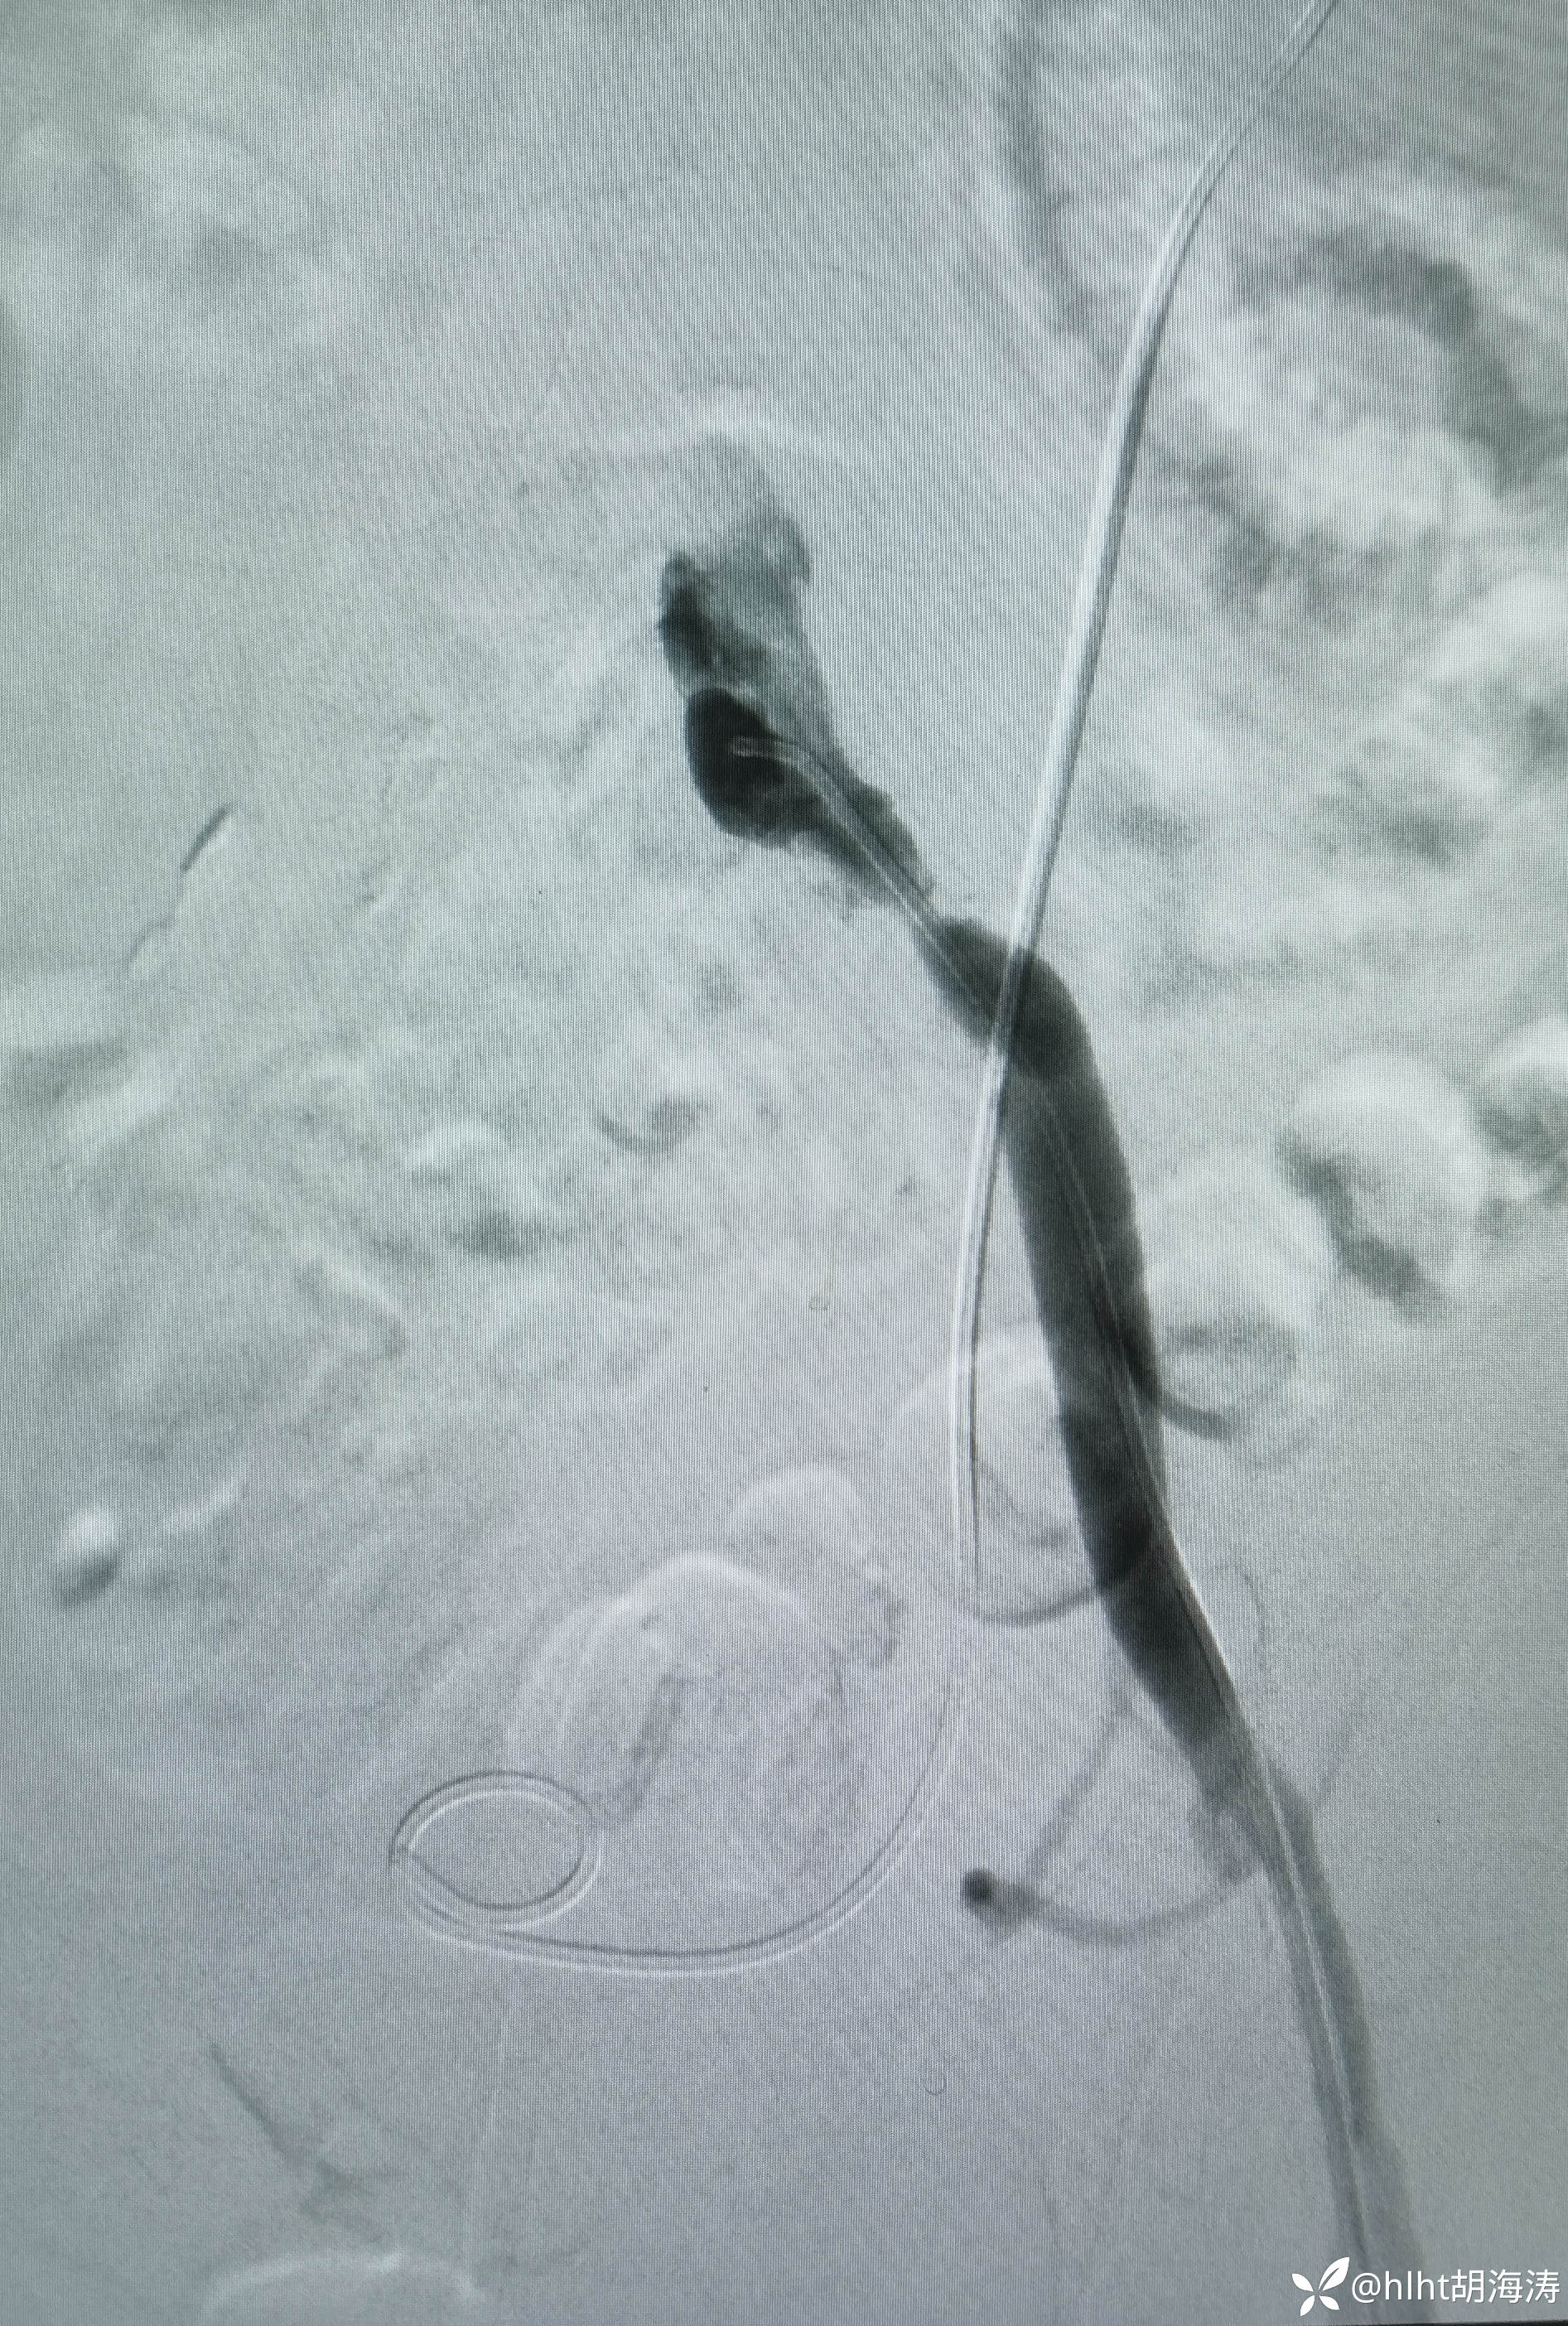

术中双侧髂外重度狭窄和右侧股浅动脉远端闭塞:

左侧髂外球囊扩张成形,然后10mm球扩支架,血流好,但是右侧血流慢

多次尝试,翻山,导丝没法进入左髂外,然后右侧腹股沟区穿刺:微创针

置入5F血管鞘:造影提示右侧髂外开口处重度狭窄